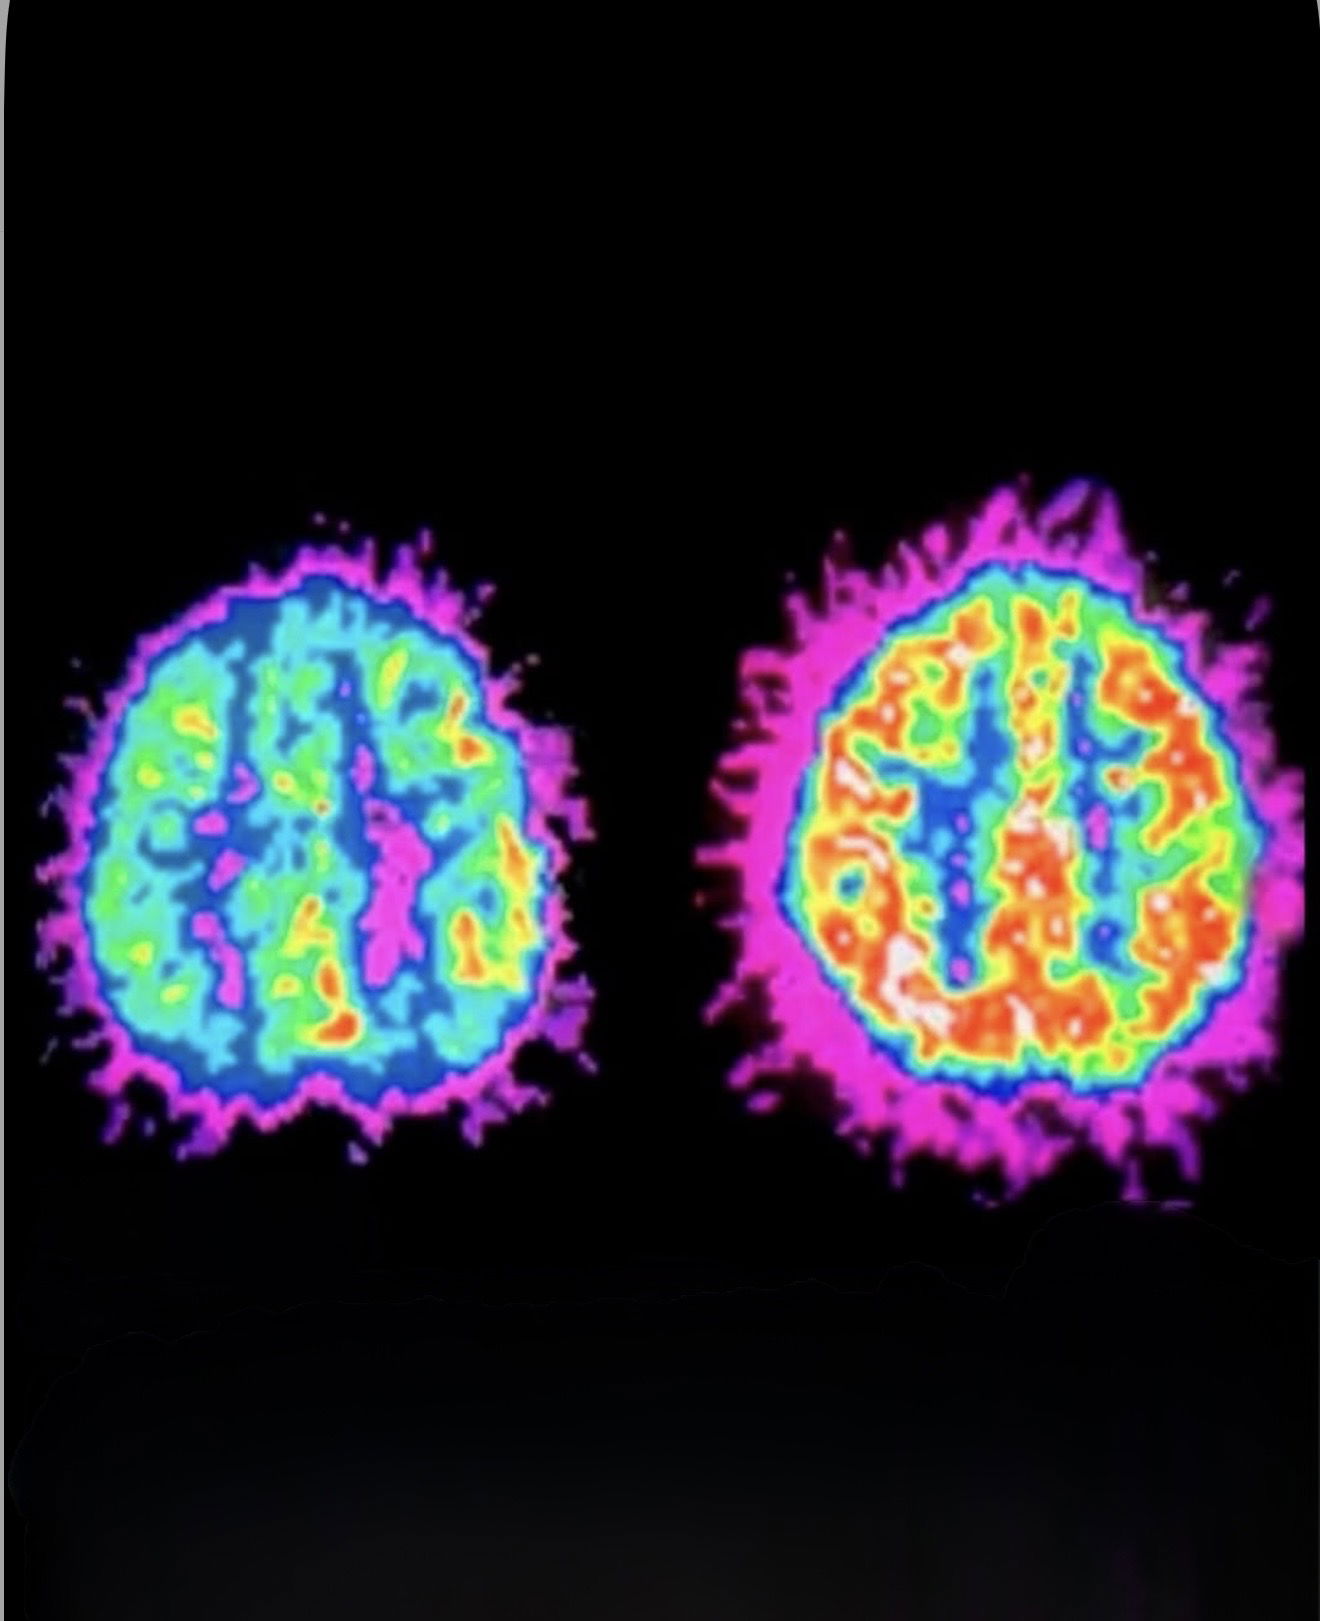

Brain scans show that people with ADHD often have differences in the prefrontal cortex — the area of the brain responsible for focus, planning, and decision-making.

Researchers explain that the dopamine system in individuals with ADHD functions differently. They tend to release less dopamine during everyday activities, making it harder to feel motivated or engaged. As a result, they often seek stronger stimulation in order to stay focused.

Studies have also found that brain regions involved in reward processing, such as the striatum, can be smaller in some individuals with ADHD.